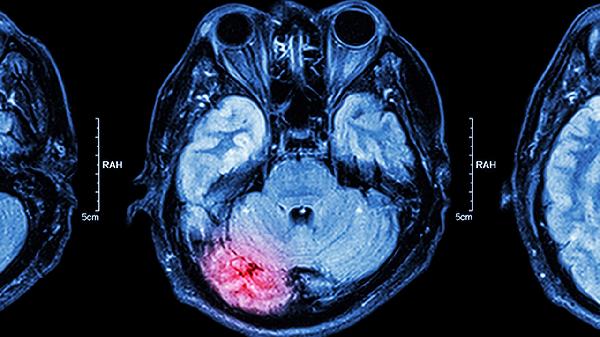

使用止血药期间建议保持充足水分摄入,每日饮水量不少于1500毫升,有助于维持血液流变学稳定。可适当进行低强度有氧运动如散步、太极拳,促进侧支循环建立。饮食上增加深海鱼类、坚果等富含不饱和脂肪酸的食物,避免高脂高盐饮食。若出现持续头痛、视物模糊等症状应立即就医,进行头颅CT或磁共振检查排除脑血管意外。用药期间定期监测血压、血脂等指标,有脑血管病史者需每3个月复查颈动脉超声。